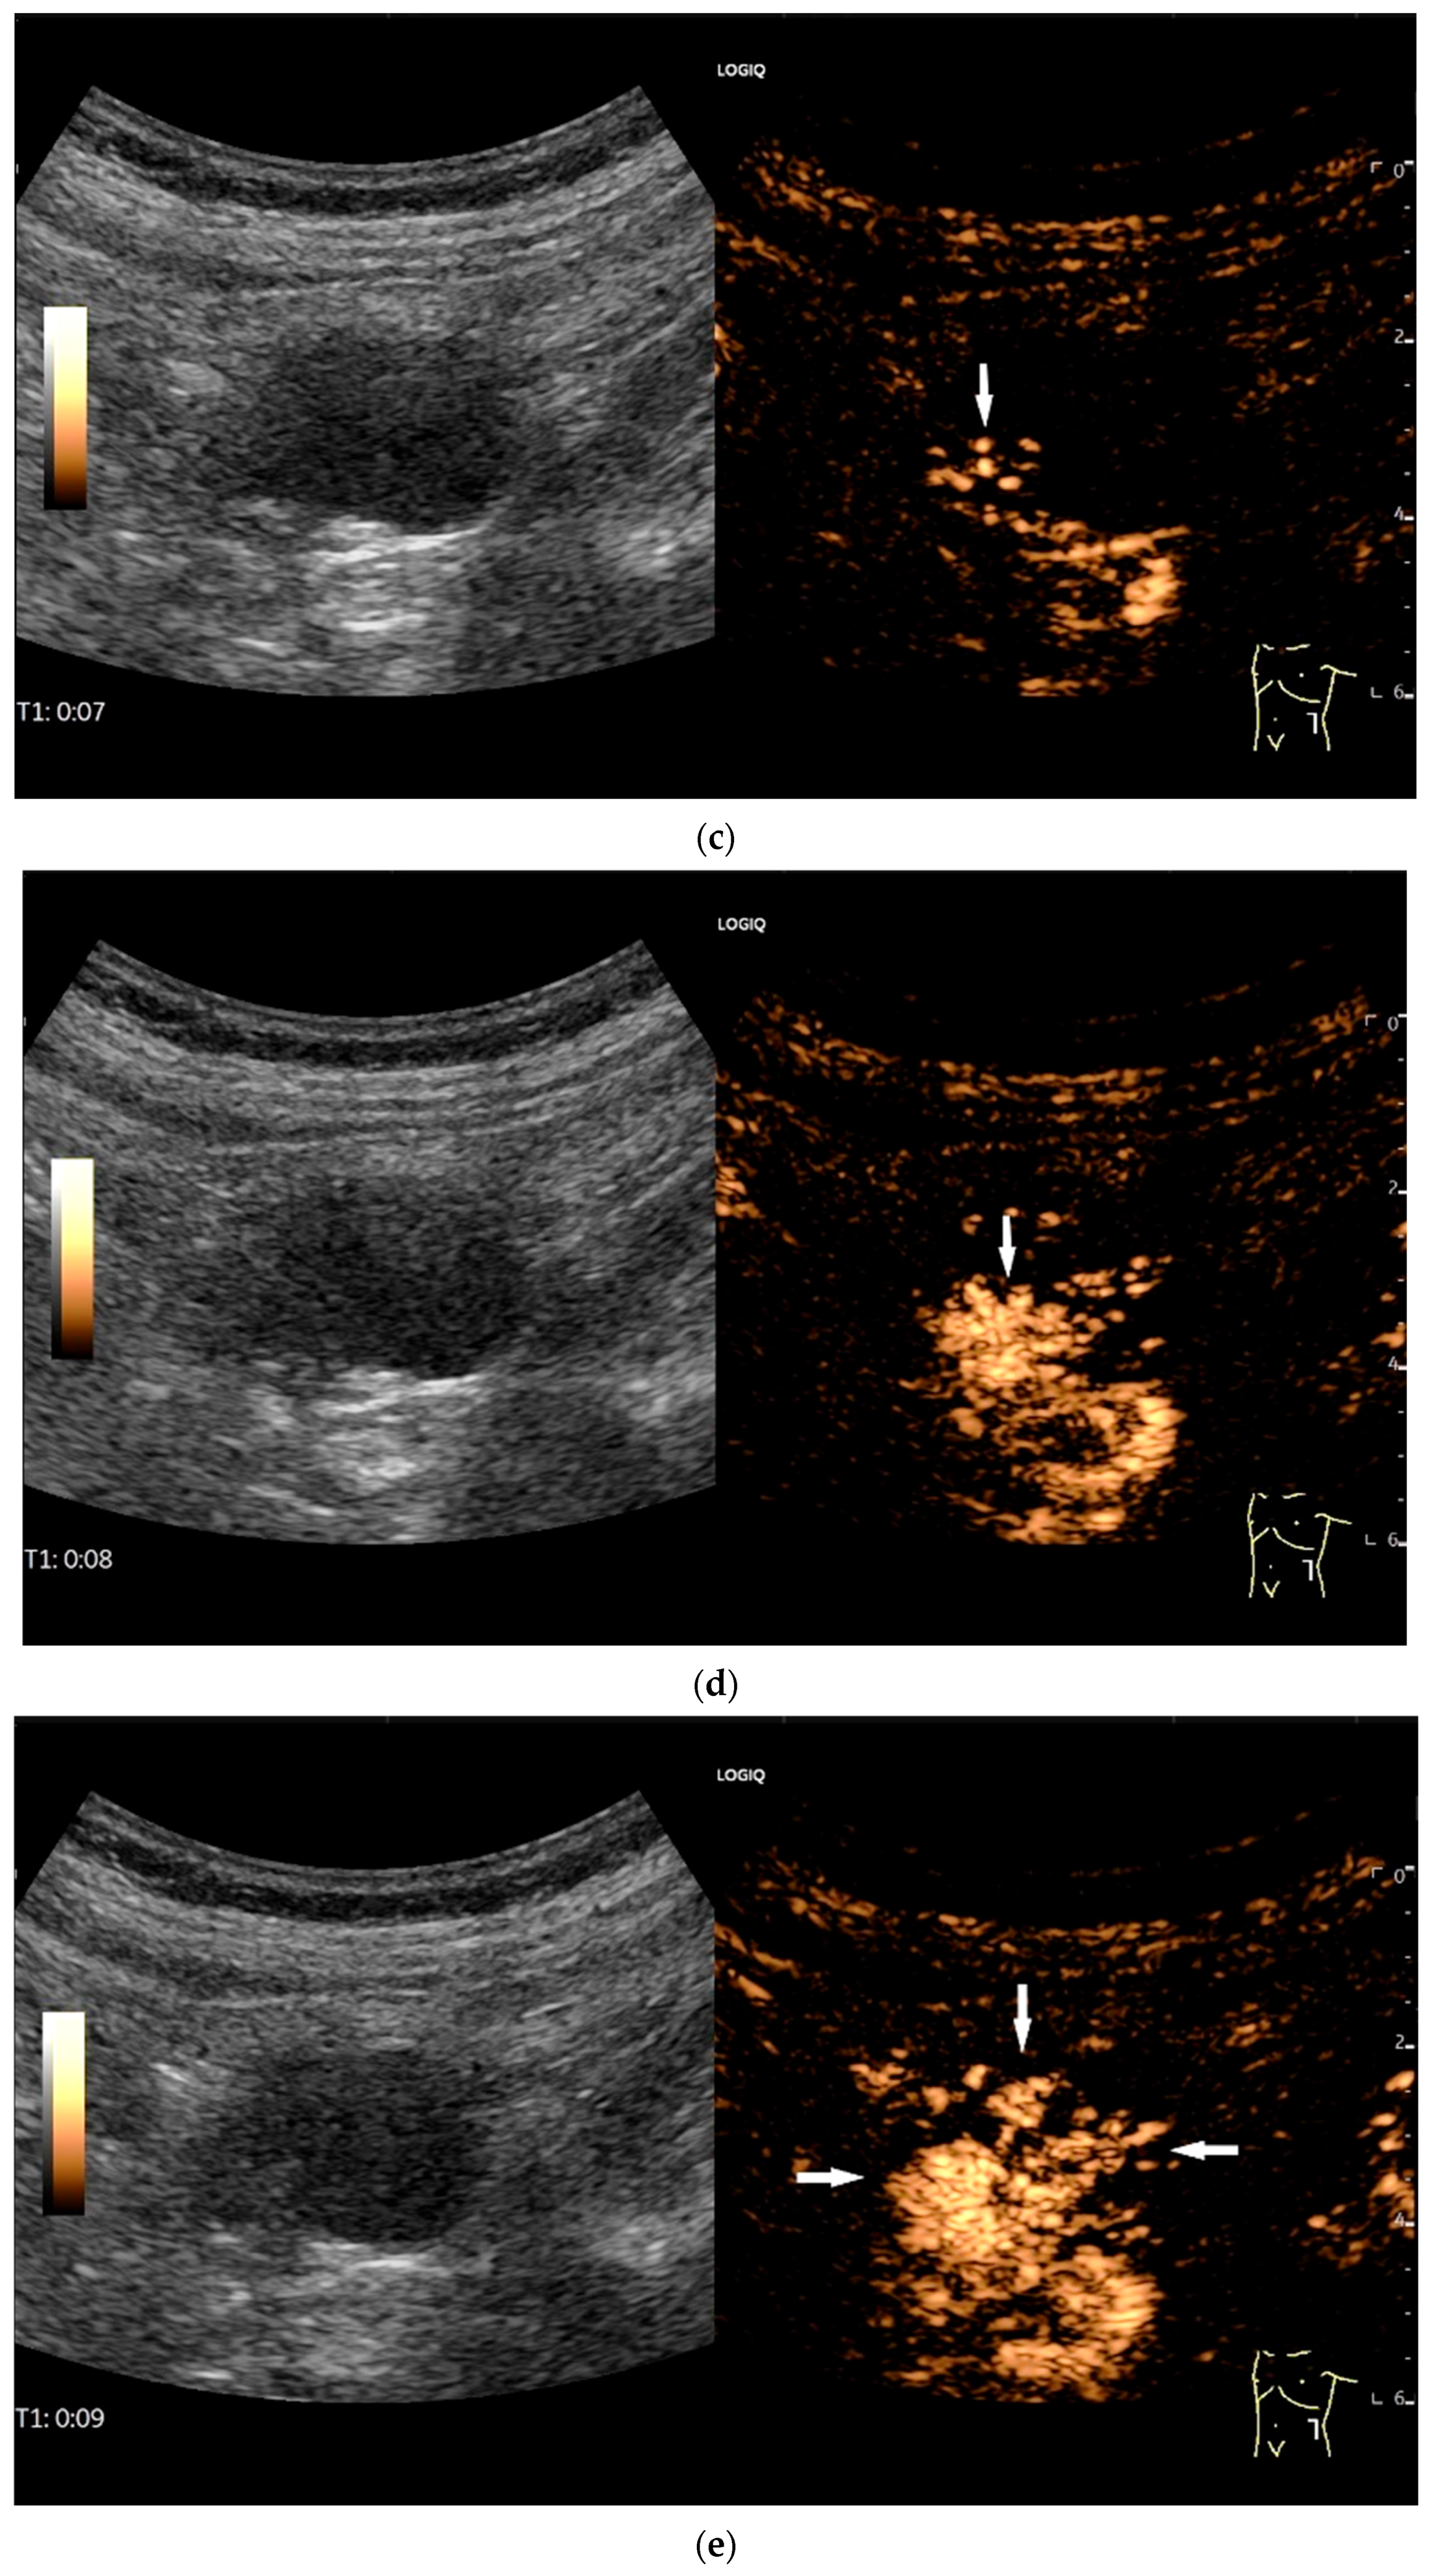

Figure 9.

Burkitt-Lymphoma. In a patient with weight loss, increased abdominal circumference, anemia, and physical weakness, the initial sonographic examination reveals an extensive tumor with intense hypoechogenicity and a connection to the jejunum in the left mid-abdomen. Despite its pronounced hypoechogenicity, a feeding vessel on CDI indicates a solid character (a). The tumor significantly thickens the wall and is intensely hypoechoic. The arrows point to the multisegmental hypoechoic wall thickenings (b). Normal wall structures are still visible (W), and the tumor extends beyond the wall (arrow) (c). In addition to delicate Kerckring folds (KF), there are significantly polypoid thickened KF with pronounced hypoechogenicity (d). The thickening of KF is very extensive (e). Wall thickening was found also in the stomach and colon and allowed endoscopic biopsy to establish the diagnosis.

Figure 10.

Diffuse large B-cell lymphoma (DLBCL). In the right mid-lower abdomen, a large, smoothly circumscribed mass is present around the ileum (“pseudo kidney sign” (a)). Using a high-resolution linear transducer, the mass appears smoothly circumscribed and almost anechoic (b). The ileum runs centrally, and the echogenic wall is clearly defined (c). This wall does not merge into the mass. Since the mass is almost anechoic, it is also difficult in different transducer positions to distinguish whether it is a liquid lesion or a solid mass (b,c). CEUS with 2.4 mL SonoVue (9 MHz linear transducer) shows homogeneous arterial enhancement (d), but the intensity decreases with time in the venous phase (e). The ileal wall enhancement centrally within the mass is more intense than that of the tumor (d,e).